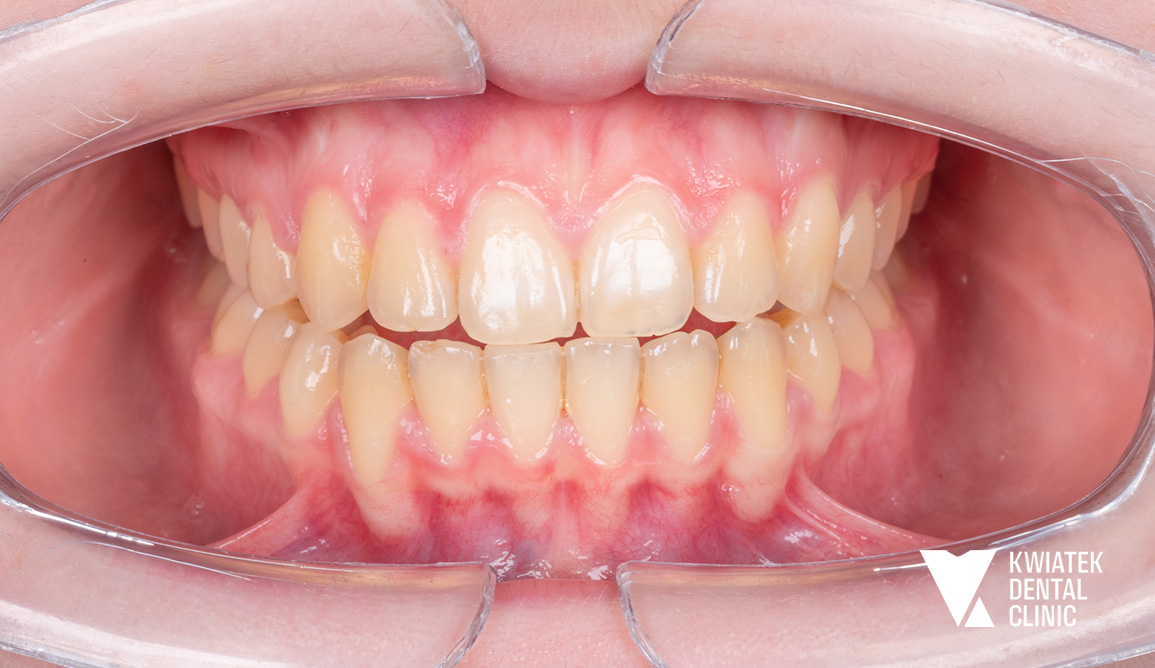

Po zakończeniu aktywnej fazy leczenia zdjęto aparat ortodontyczny oraz wdrożono etap retencji - retainer stały w łuku dolnym oraz retainery ruchome dla obu łuków.

Uzyskano:

Efekt końcowy to harmonijny, naturalny uśmiech oraz poprawa funkcji narządu żucia. Pacjentka pozostaje pod opieką kontrolną, a zastosowana retencja zapewnia trwałość uzyskanych rezultatów.